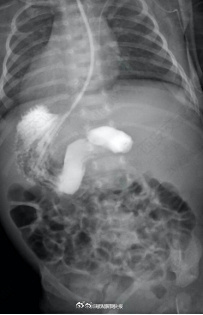

近日,西安交大一附院接诊了一名“镜面宝宝”,系36周早产儿,出生体重2.5kg,反复吐奶,腹部超声示内脏反位、十二指肠不全梗阻,心脏超声提示右位心。在辗转2家医院后仍未明确病因,且呕吐逐渐加重,随后转至交大一附院治疗。“镜面宝宝〞解剖结构特殊,加之低体重儿微创手术视野有限,手术难度很大。经历3小时手术,宝宝转入新生儿重症监护室治疗,17天后痊愈出院。(健康时报)